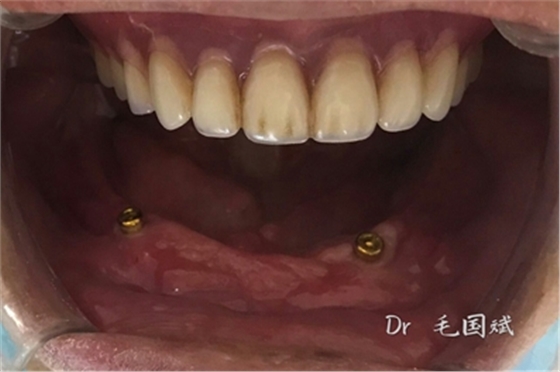

毛國斌種植病例——群討論分享